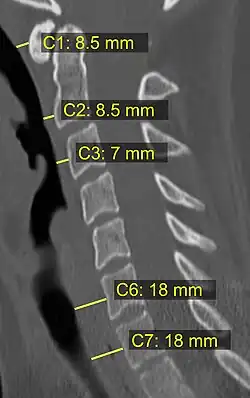

On CT scan or X-ray, a cervical fracture may be directly visualized. In addition, indirect signs of injury by the vertebral column are incongruities of the vertebral lines,[7] and/or increased thickness of the prevertebral space:[8]